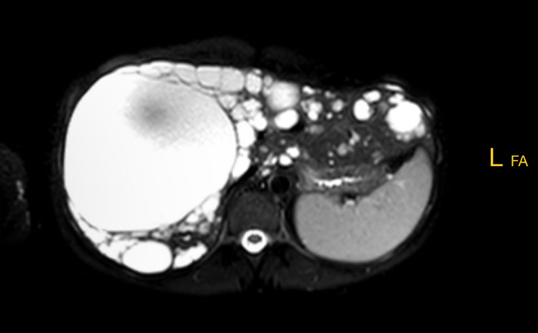

Die Polyzystische Lebererkrankung (PLD) ist eine gutartige, aber chronisch fortschreitende Erkrankung, bei der sich zahlreiche mit Flüssigkeit gefüllte Zysten in der Leber bilden.

Diese Zysten entstehen durch eine Fehlentwicklung der Gallengänge und können im Laufe der Jahre an Zahl und Größe zunehmen. Dadurch vergrößert sich das Lebervolumen – manchmal um ein Vielfaches – und es kann zu mechanischen Beschwerden und Funktionsstörungen kommen.